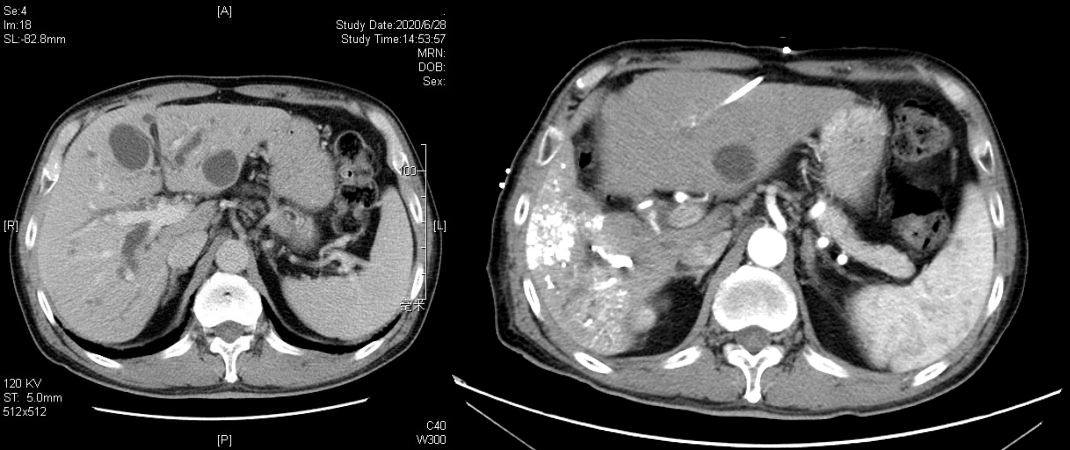

PVE术前(左)后1月(右)CT增强左右肝比较:左肝明显增生,右肝明显萎缩